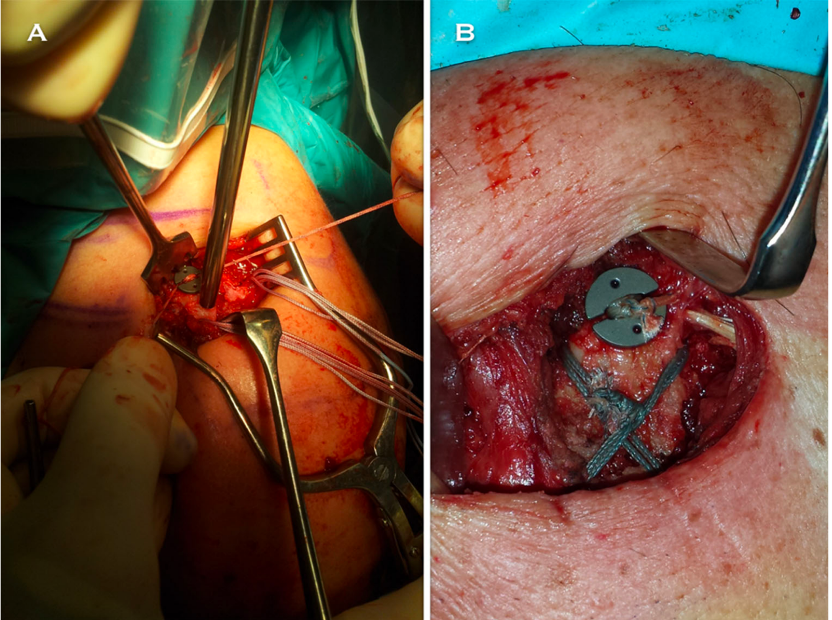

铆钉结合张力带克氏针固定

铆钉结合张力带克氏针固定后再次骨折,但转化为中段骨折,予以钢板固定

关节镜下袢钢板固定结合缝线固定骨折